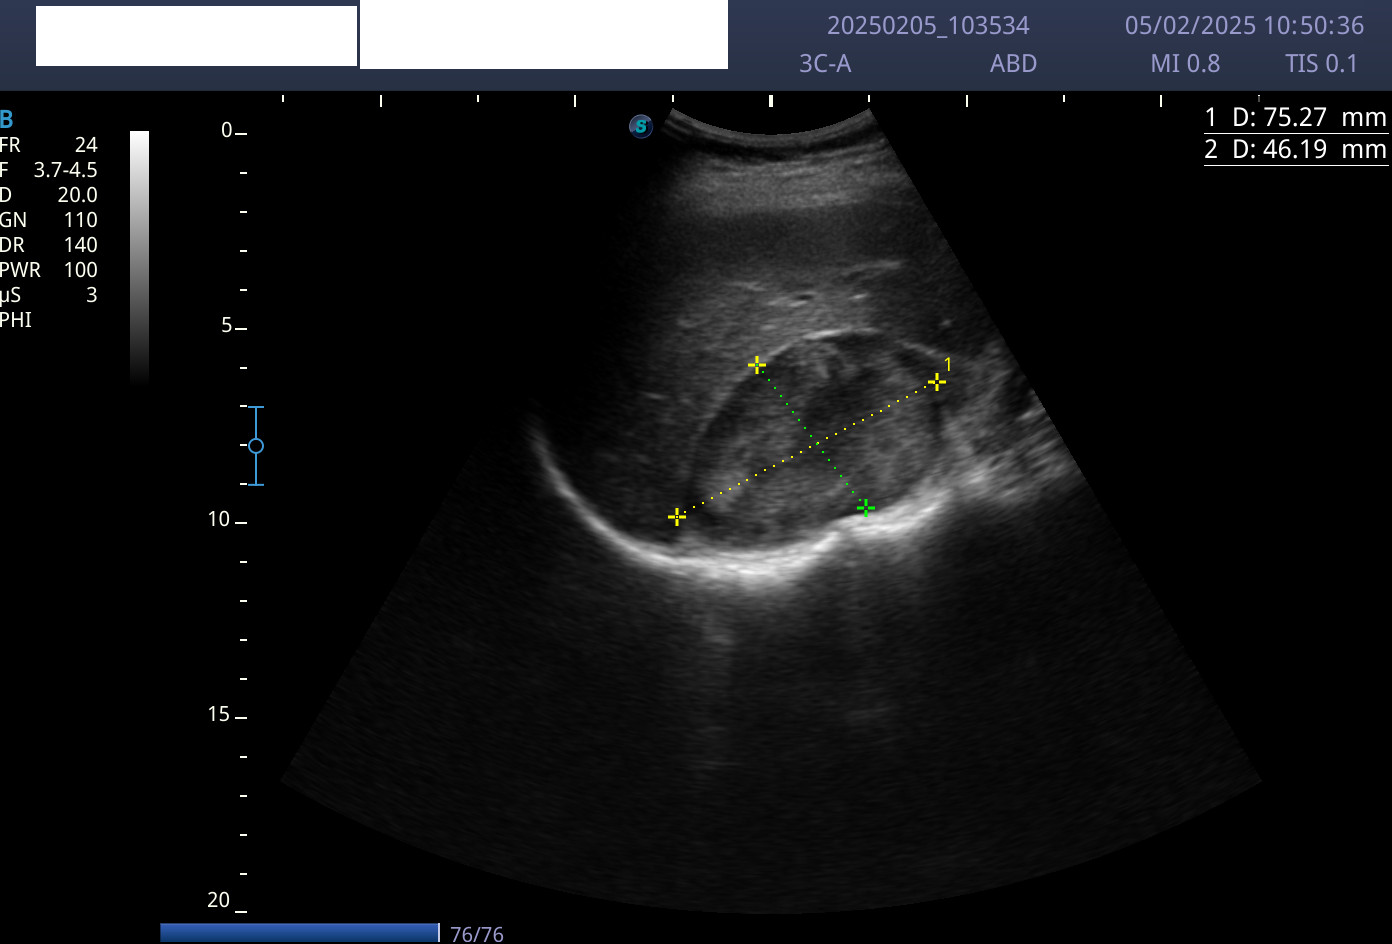

Como venía en seguimiento por dolor lumbar derecho, se procedió a realizar una ecografía de abdomen. Se encontró una masa sólida heteroecogénica, con alguna calcificación, bien delimitada, a nivel suprarrenal derecho de unos 60 x 80 mm.

Juicio clínico: tumor en la glándula suprarrenal derecha con metástasis cutáneas.

Diagnóstico diferencial: neoplasia adrenal maligna primaria (carcinoma adrenal o feocromocitoma) versus metástasis de carcinoma de pulmón, mama, melanoma, digestivo o renal. En cuanto a las lesiones cutáneas, el diagnóstico diferencial incluiría procesos infecciosos, traumáticos (hematoma organizado) o lesiones neoplásicas malignas (sarcoma, linfoma o metástasis cutáneas).